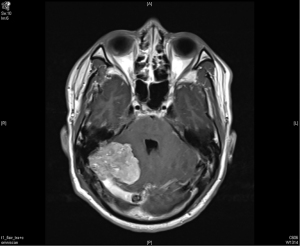

A 36-year-old man with no significant past medical history presented to the outpatient department in November 2009 with fever up to 40 degrees Celsius and headache over the posterior head region for 2 days. With the suspicion of meningitis, a brain magnetic resonance imaging (MRI) was done which showed a 57 mm × 40 mm × 70 mm lobulated extra-axial tumor over the right cerebellar tentorium with focal mass effect and resultant mild secondary non-communicating obstructive hydrocephalus (Figure 1). The possibility of extra-axial tumor such as pedunculated meningioma was considered. He underwent an excision of the lobulated mass which was sent for histopathological diagnosis. This revealed randomly oriented monomorphous tumor cells with little intervening fibrosis. The cytoplasm was scant and cell borders were indistinct. The nuclei were round to oval with moderately dense chromatin, inconspicuous nucleoli to focal areas of vesicular nuclei and mild to moderate atypia. The mitotic activity was mildly increased. No necrosis was seen in the sections. Focal mild hemorrhage and embolization material in vessels were noted. The immunohistochemical study demonstrated positive for CD34, CD99, and reticulin along with an increased Ki-67 proliferative index suggestive of a HPC.